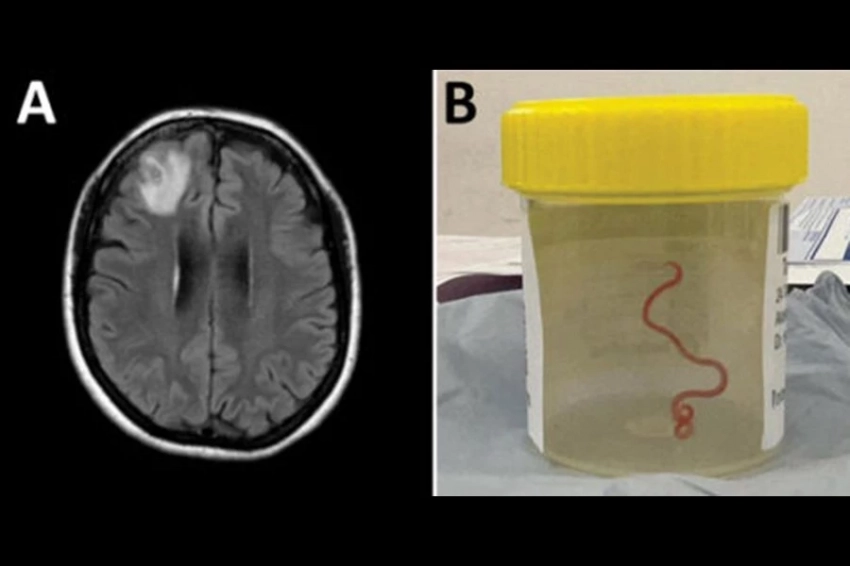

Проведенная магнитно-резонансная томография выявила аномалии в головном мозге, требующие хирургического вмешательства. Однако то, с чем столкнулись врачи, вызвало удивление. Доктор Санджай Сенанаяке говорит: «Нейрохирург, конечно, не ожидал найти червя. Нейрохирурги часто сталкиваются с инфекциями головного мозга, но это было действительно редким открытием.»

Этот случай побудил команду больницы провести дальнейшие исследования. Важным вопросом было определение типа круглого червя и принятие решения о необходимости дополнительного лечения пациентки. Оказалось, что это паразит Ophidascaris robertsi, который обычно обитает у питонов. Чрезвычайно редко данный паразит встречается у человека, и это первый в истории случай его обнаружения у человека.